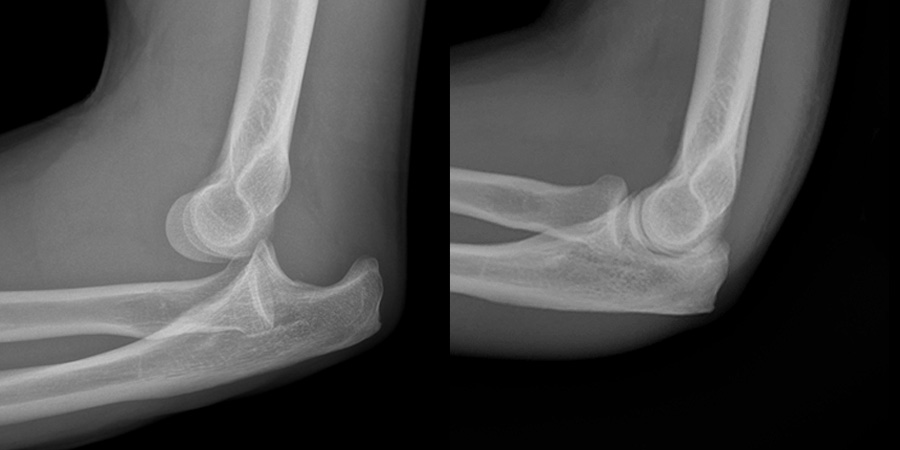

This dislocation (and subsequent reduction) can lead to injury to what nerves?

Ulnar (MC)

Median